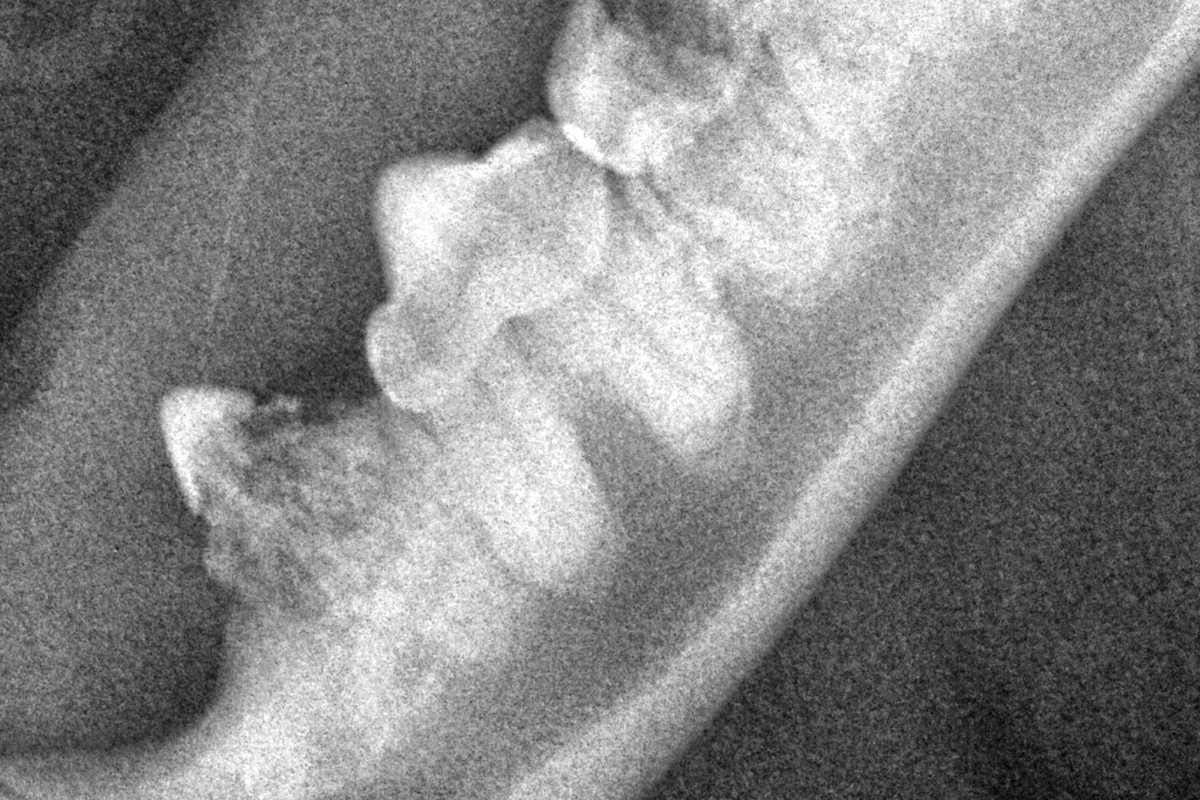

Кошка британская, рентген

Тем не менее, на стадии разрушения коронки зуба и ее эмали, а так же разрушение цемента корня зуба, реальной помощью пациенту будет удаление этих зубов, это является сложной процедурой и должна проводиться только опытными ветеринарными стоматологами с обязательной рентгенографической диагностикой во время проведения процедуры удаления зубов.